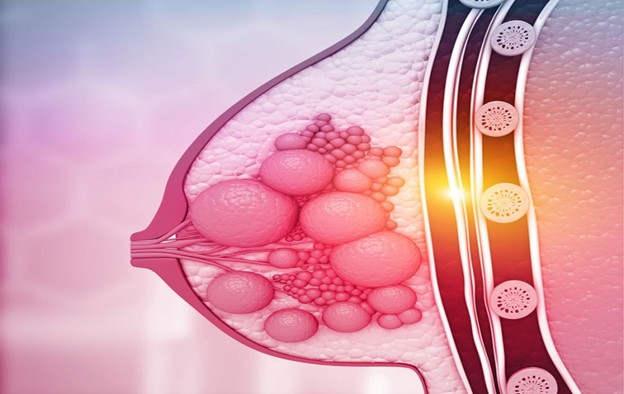

Meme Kanseri Tedavisi

Meme kanseri tedavisi ve meme rekonstrüksiyonu, oldukça karmaşık bir süreçtir ve bazı durumlarda ilaç tedavileri veya diğer tıbbi müdahaleler gerekebilir.

Tamoksifen, özellikle hormon reseptör pozitif meme kanseri tedavisinde kullanılan bir ilaçtır. Hormon reseptör pozitif meme kanseri, östrojen ve/veya progesteron hormonlarına duyarlı olan kanser türüdür. Tamoksifen, bu hormonların kanser hücrelerinin büyümesini teşvik etmesini engelleyerek çalışır. Bu nedenle, hormon reseptör pozitif meme kanseri olan hastalarda tamoksifen, kanserin tekrarlama riskini azaltmak ve tedaviyi desteklemek için kullanılır.